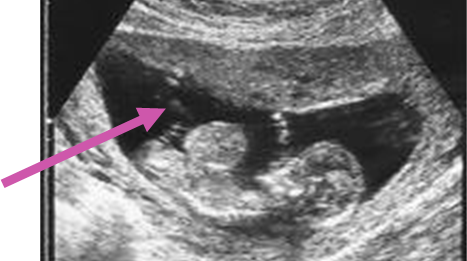

CDH